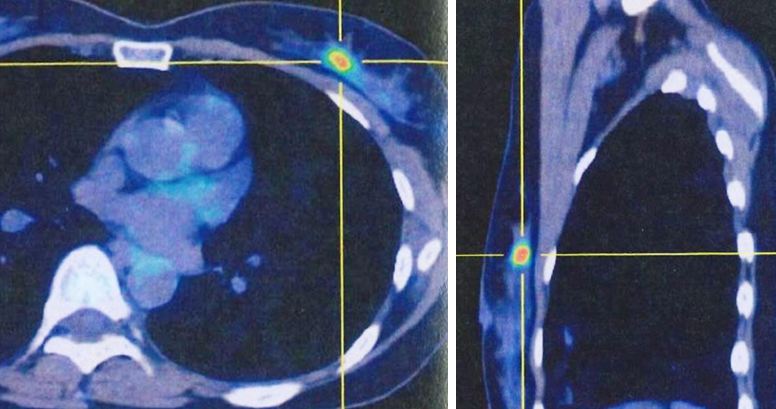

3. Whole body PET-CT scan. This was done on 17 September 2022.

Two small hypermetabolic nodules at 12 o’clock and 1 o’clock positions of left breast are consistent with biopsy proven malignancy.

A group of several minimally FDG avid tiny irregular nodules in left lung are more likely inflammatory than neoplastic judging from their distribution.

Small hypermetabolic focus in right corn of uterine cavity can be inflammatory change, but malignancy is not excluded. Gynecological evaluation is recommended.

Otherwise, no metabolic evidence of distant metastasis.